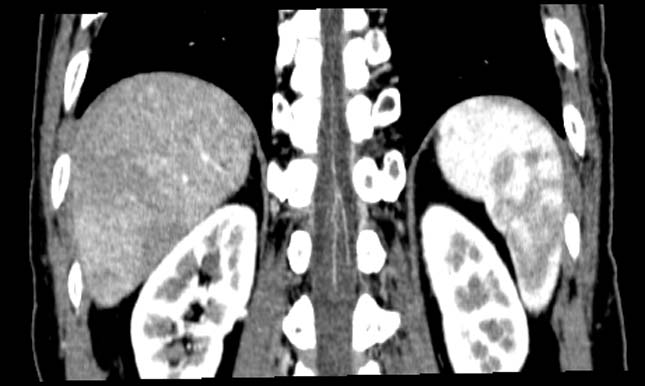

0.5sec., 2mmx4, Pitch 3.5, 11.5 sec., 150 mAs, SureStart, BHC

MPR